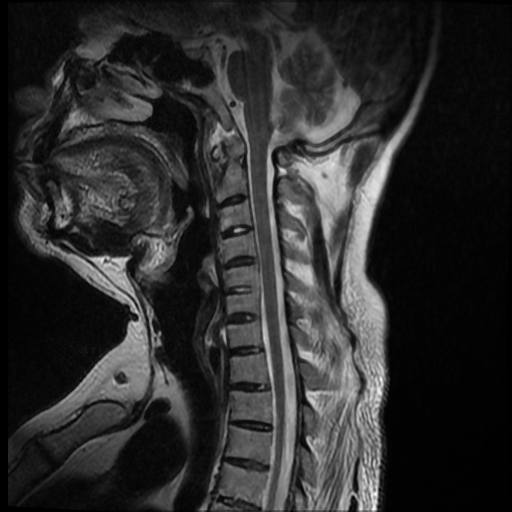

La espondilitis anquilosante (EA), es una enfermedad autoinmune inflamatoria crónica que afecta principalmente a las articulaciones de la columna vertebral y causa dolor crónico severo, afecta principalmente a las articulaciones de la columna, las articulaciones sacroilíacas y los tejidos blandos adyacentes, como los tendones y los ligamentos. En casos más avanzados, esta inflamación puede dar lugar a fibrosis y calcificación, dando como resultado la pérdida de flexibilidad y la fusión de la columna, asemejándose a un “bambú” con una posición inmóvil. Este caso se enfoca a paciente de 37 años de edad, que manifiesta rigidez y perdida de la linealidad de la columna cervical, encontrando a través del estudio de MRI calcificación de los ligamentos anterior y posterior de la columna cervical, más fusión de vértebras cervicales.

Ankylosing spondylitis (AS) is a chronic inflammatory autoimmune disease that primarily affects the joints of the spine and causes severe chronic pain. It primarily affects the joints of the spine, the sacroiliac joints, and adjacent soft tissues such as tendons. and the ligaments. In more advanced cases, this inflammation can lead to fibrosis and calcification, resulting in loss of flexibility and fusion of the spine, resembling a “bamboo” with an immobile position. This case focuses on a 37-year-old patient, who manifests rigidity and loss of linearity of the cervical spine, finding through the MRI study calcification of the anterior and posterior ligaments of the cervical spine, plus fusion of cervical vertebrae.

Se observa perdida de la lordosis normal de la columna cervical.

Se observa hipo intensidad del ligamento longitudinal anterior y posterior de la columna cervical, también se observa perdida de la movilidad y rigidez de la misma, los ligamentos interespinosos se ven hipointensos en T2 y en T1, al igual que el pliegue nucal, lo que sugiere calcificación de estas estructuras anatómicas.

Se observa fusión de las vertebras cervicales 5-6 y 6-7, dando la apariencia de bambú.

• Perdida de la lordosis

• Ligamentos espinales anterior, posterior, interespinosos y pliegue nucal calcificados

• Fusión de vertebras cervicales 5-6 y 6-7.